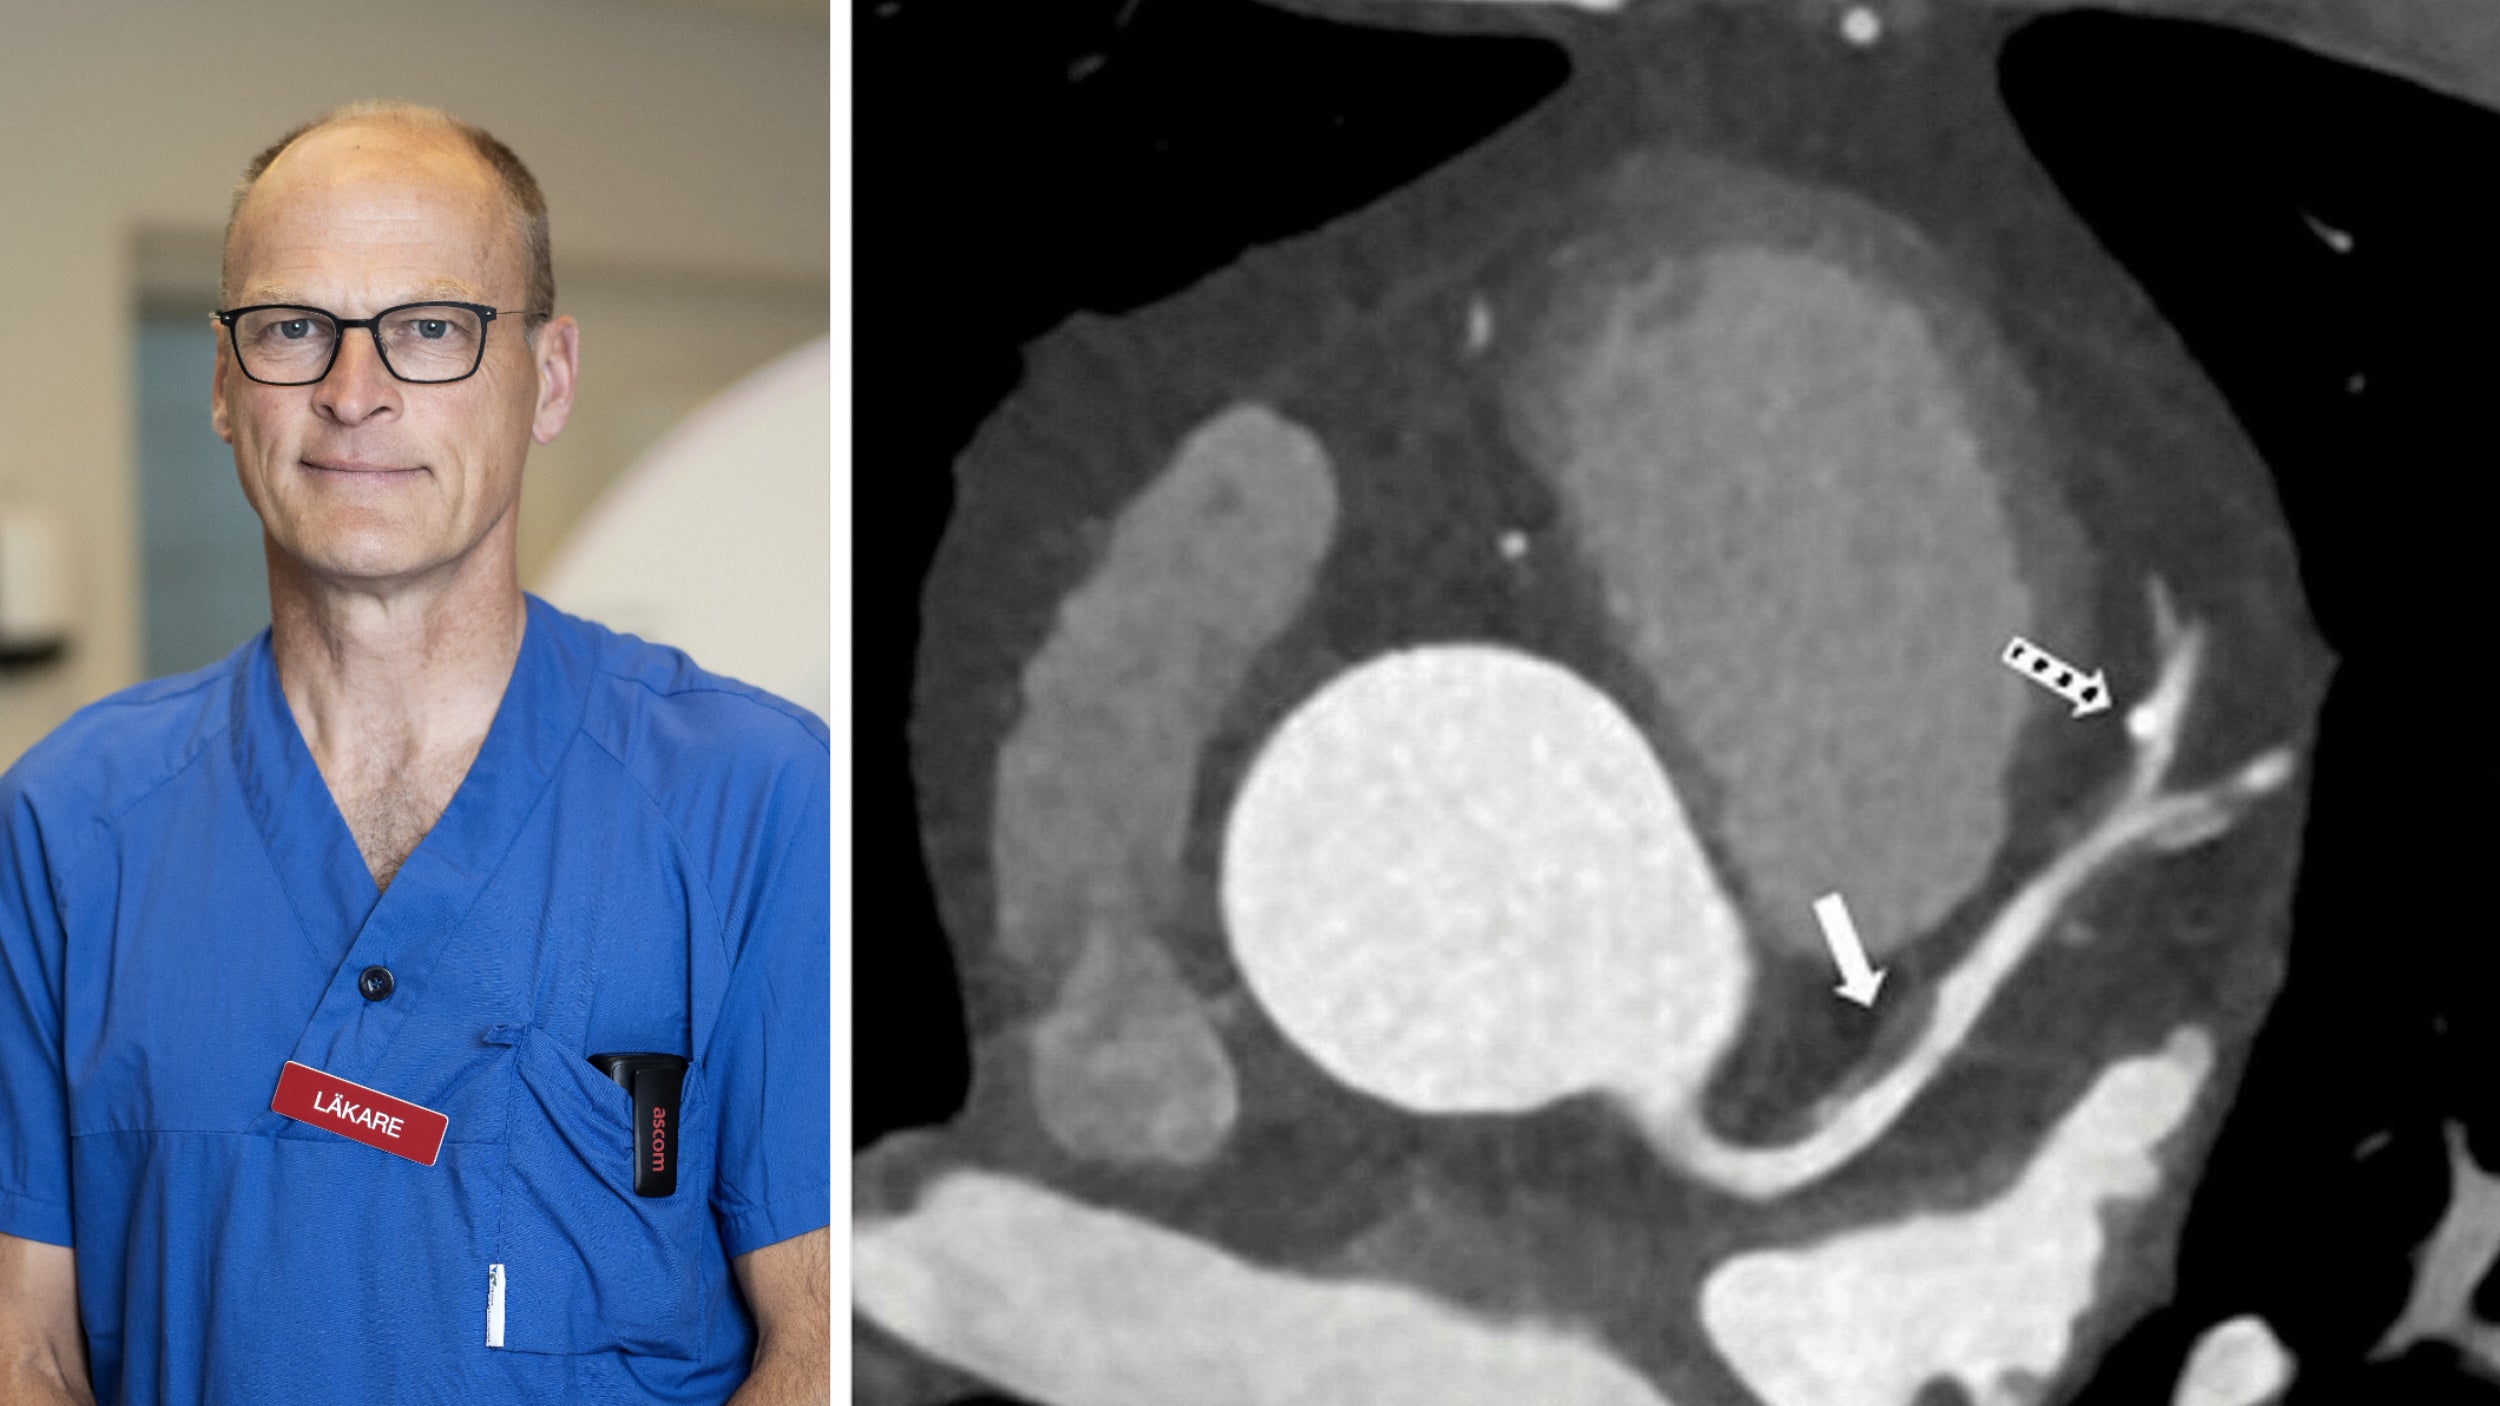

En ny studie publicerad i tidskriften Jama visar att användningen av datortomografi, i kombination med kontrastmedel, kan förbättra möjligheten att bedöma risken för hjärt-kärlsjukdom hos personer som annars verkar friska.

Studien, som genomfördes i Sverige, är den första i sitt slag att påvisa att skiktröntgen kan vara ett effektivt verktyg för att upptäcka tysta kranskärlsförträngningar. Detta kan i sin tur leda till att dessa individer får en mer noggrann bedömning av huruvida de behöver primärpreventiv behandling.

Genom att identifiera dessa förträngningar tidigare, kan vården potentiellt förhindra framtida hjärtproblem och förbättra patienters livskvalitet. Resultaten av studien kan ha stor betydelse för hur vi ser på riskbedömning och förebyggande åtgärder inom hälso- och sjukvården.

Dessa fynd understryker vikten av att använda avancerade diagnostiska verktyg som skiktröntgen för att få en mer komplett bild av en patients hjärtstatus, särskilt hos dem som annars skulle kunna anses vara i riskgrupp utan uppenbara symptom.